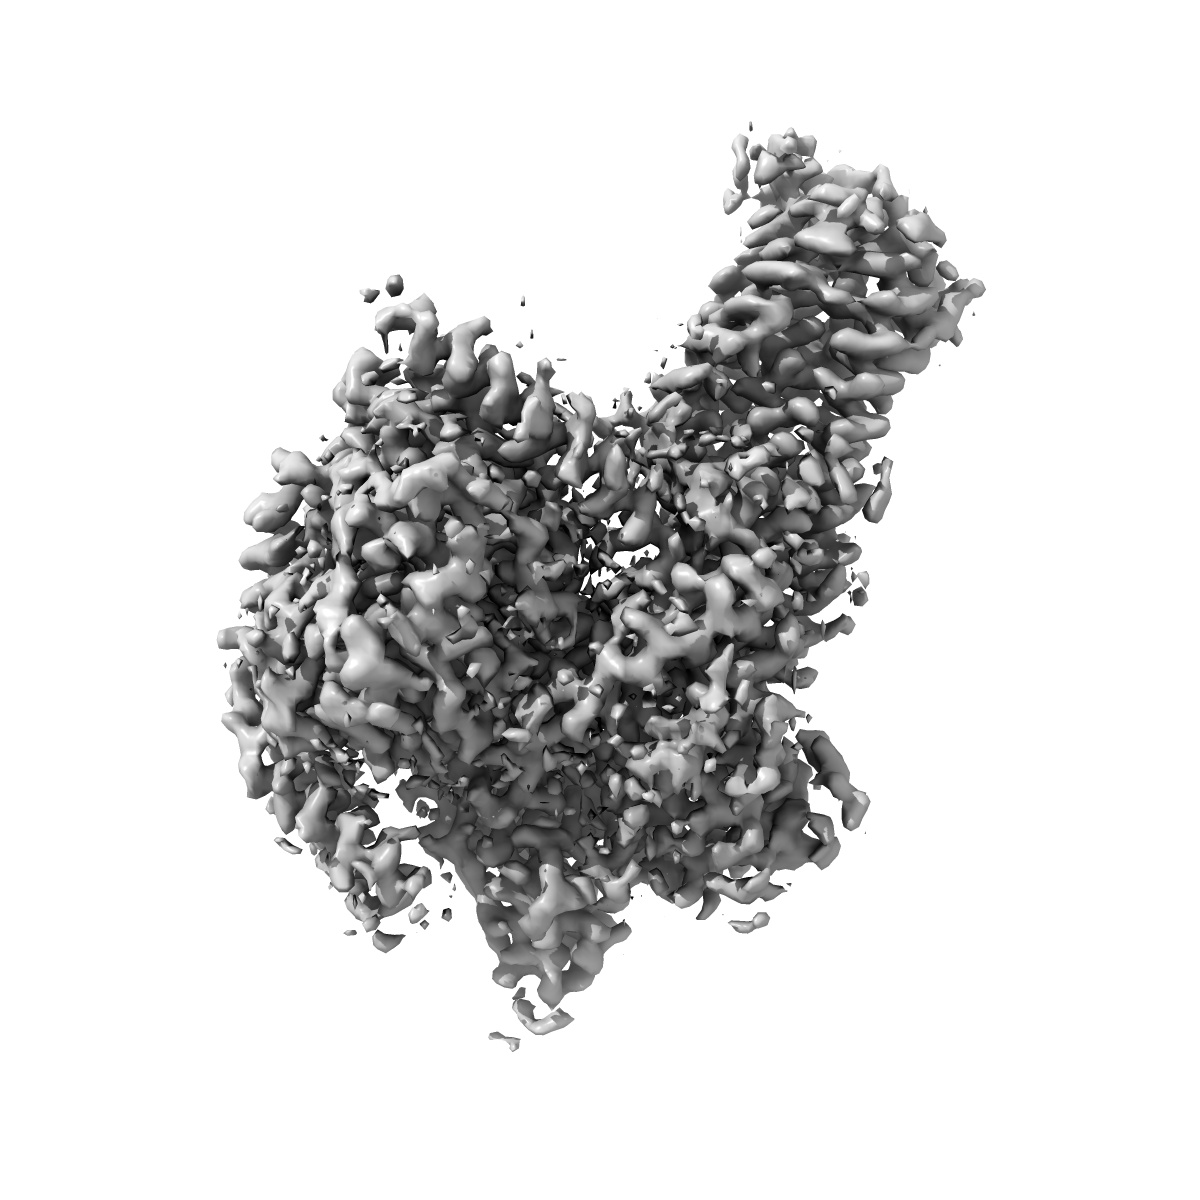

Cryo-EM structure of the Taprenepag-bound EP2-Gs complex

Single-particle2.8 Å

Sample: Taprenepag-bound EP2-Gs complex

Fitted models: 7cx3

Ligand recognition, unconventional activation, and G protein coupling of the prostaglandin E 2 receptor EP2 subtype.